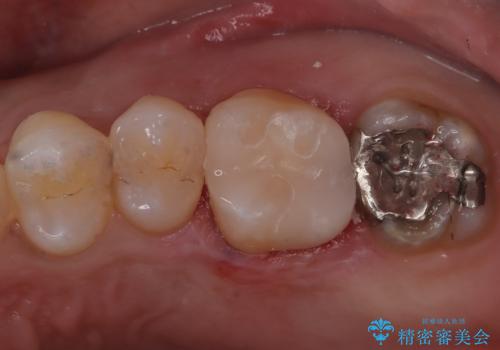

奥歯の被せもの

- 食事中に奥歯の材料が欠けたとのことで来院された患者さまです。

咬合力の負担が強いため被せものによる治療を行っております。

咬合力が強くかかる部分には欠けるリスクのほとんどない金属を用いることが最良ですが審美性に劣ります。

今回は白い材料での修復を希望されたため、欠けるリスクが高いセラミックインレーは避け、セラミッククラウンにて治療を行いました。